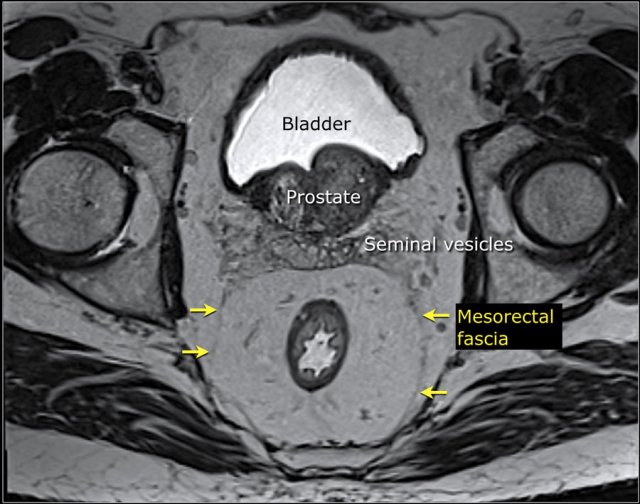

The mesorectal fascia (MRF) is a thin fibrous structure that encloses the mesorectal compartment and comprises the anticipated resection plane in TME surgery.

On T2-weighted MRI the mesorectal fascia can be recognized as a thin hypointense line surrounding the mesorectum.

When a tumor directly invades the MRF or the margin between the tumor and MRF is ≤ 1 mm, the MRF is involved.

In these cases routine TME would induce a risk for local recurrence and neoadjuvant treatment will be required to induce tumor downsizing to retract the tumor from the MRF aiming to achieve a tumor-free resection margin.

When describing involvement of the MRF, you should always describe the location of involvement (e.g., “MRF+ at … o’clock” or “MRF+ at the left anterior side”)